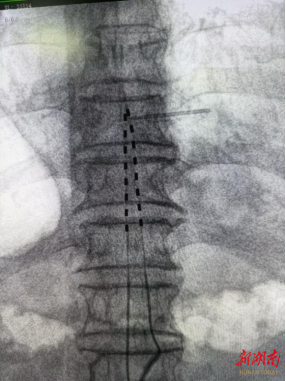

经过详尽的术前准备,并向龙嗲详细解释手术原理,李勇辉团队随即为患者安排了一期微创手术,术后即刻返回病房,为龙嗲开机测试,并调整参数,疼痛区域被温和酥麻感替代,nrs评分降至2-3分。

一期测试:手术微创,费用较低,在dsa引导下电极植入,7天刺激器外挂测试,疼痛缓解>70%;